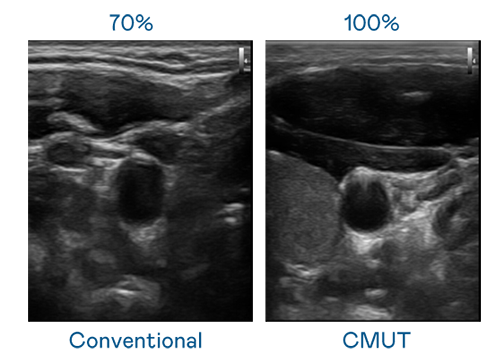

CMUT 技术是一种用电容式微机电元件来产生超音波讯号的技术。与传统 PZT 压电式技术相比,CMUT 频宽增加 30%,更宽频的超音波讯号让影像解析度大幅提升,是实现高影像品质医疗超音波扫描、促进精准医疗发展的关键技术。

超音波影像的解析度高低,首先取决于探头能发出的讯号频宽。永利娱乐城 CMUT 可提供高清晰的超音波讯号,提供高频宽、高灵敏度、影像纹理细节更高的超音波影像,协助医护人员缩短影像判读时间及利用精准的医疗影像进行诊断。